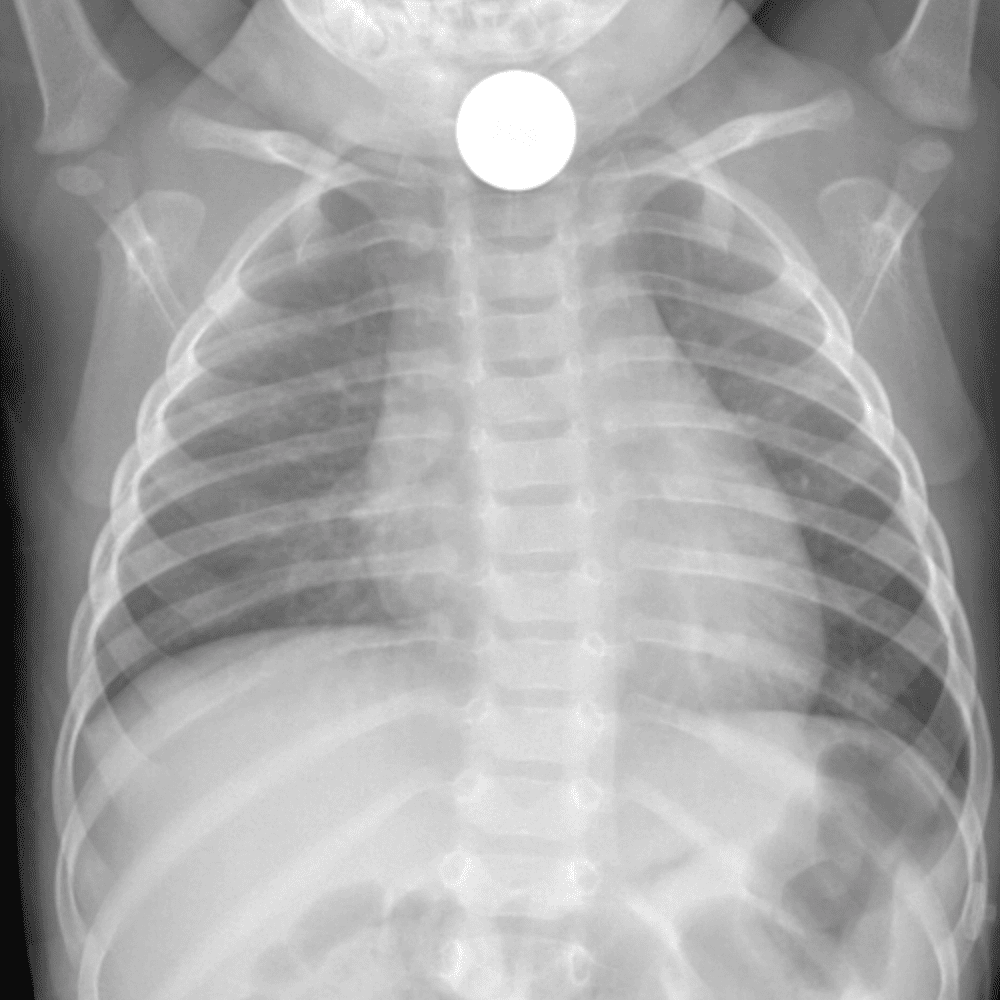

Peds Chest

Practice

Simulates call by including subtle or difficult cases and some normals.

50 cases